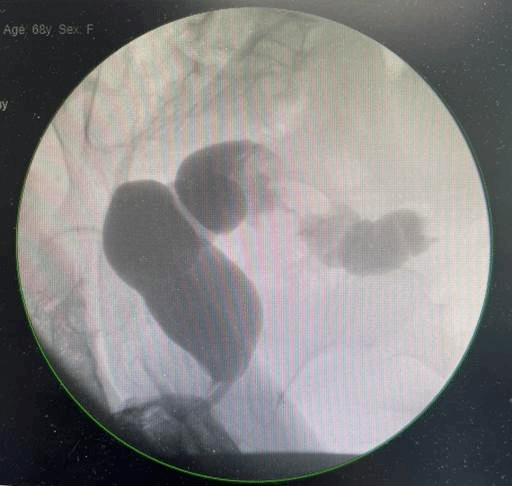

直肠占位伴狭窄

68岁的黄女士因感染新冠病毒导致肺炎来到ac米兰官网中文网站一院治疗。入院后,完善相关检查发现左肾和直肠两处脏器分别有原发占位性病变,需要尽快手术治疗。

左肾占位